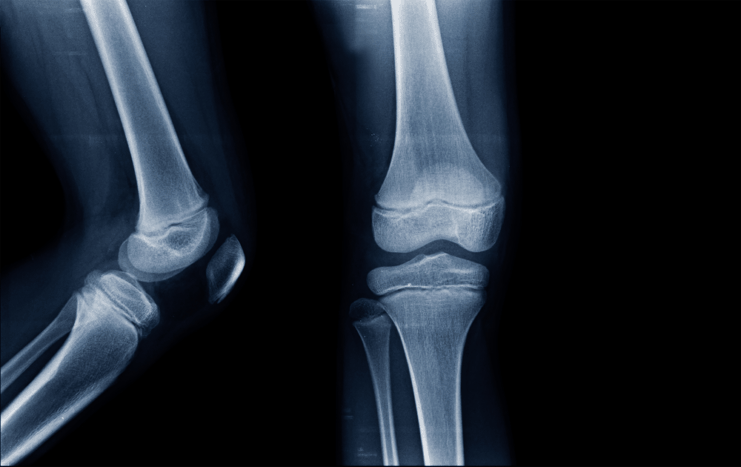

ခန္ဓာကိုယ်ကို အရိုး၊ ကြွက်သား၊ အကြော၊ အရွတ်၊ အရိုးနုတို့နဲ့ ဖွဲ့စည်းထားတာပါ။ ဒီအစိတ်အပိုင်းတွေ အားလုံး ကျန်းမာပြီး ကိုယ့်တာဝန်ကိုယ်ကျေမှ ခန္ဓာကိုယ်က အကောင်းဆုံးလှုပ်ရှားနိုင်မှာပါ။ အဆစ်နေရာတွေကို ကောင်းကောင်းကွေးနိုင် ဆန့်နိုင်စေဖို့အတွက် အဓိကလုပ်ဆောင်နေတဲ့ အစိတ်အပိုင်းလေးတစ်ခုလည်း ရှိပါတယ်။ ဒါကတော့ အရိုးနုပါ။ အရိုးနုလေးတွေ ကျန်းမာနေလို့သာ ခန္ဓာကိုယ်က အဆစ်တွေကို အကောင်းဆုံးအသုံးချပြီး ကွေးနိုင်ဆန့်နိုင်တာပါ။ ဒီတစ်ခေါက်တော့ ကွေးလိုက်ဆန့်လိုက်တိုင်းမှာ အဆစ်ထဲကနာတာ ၊ တကျွတ်ကျွတ်မြည်သံတွေ ထွက်တာကနေ ကင်းဝေးစေဖို့အတွက် အရိုးနုလေးတွေ ကျန်းမာအောင် စားပေးသင့်တဲ့ အစားအစာလေးတွေအကြောင်း ပြောပြပေးပါရစေနော်။

အရိုးနုက ဒီလောက်ထိအရေးပါတာပါ

အရိုးနုဆိုတာ ခန္ဓာကိုယ်အတွက် မရှိမဖြစ်အရေးပါတဲ့ အစိတ်အပိုင်းတွေထဲက တစ်ခုပါ။ တွယ်ဆက် တစ်ရှုးလို့သိထားကြပြီး ခန္ဓာကိုယ်နေရာအနှံ့မှာ ရှိနေနိုင်ပါတယ်။ အရိုးနုလေးတွေ ကျန်းမာ ကောင်းမွန်နေလို့သာ ကိုယ်ခန္ဓာအစိတ်အပိုင်းတွေကို လိုသလို အကွေးအဆန့်လုပ်ပြီး လှုပ်ရှားနိုင်နေ တာပါ။ တကယ်လို့ အရိုးနုလေးတွေသာ ထိခိုက်ပျက်စီးသွားမယ်ဆိုရင် ရောင်ရမ်းနာကျင်တာ၊ အကြော တွေ တင်းတောင့်နေတာ၊ နာကျင်တာတွေခံစားရနိုင်ပါတယ်။ ဒီအခြေအနေကနောက်ပိုင်းမှာ အဆစ်အမြစ်တွေ ရောင်ရမ်းနာကျင်တာမျိုးအထိ ဖြစ်စေနိုင်ပါတယ်။